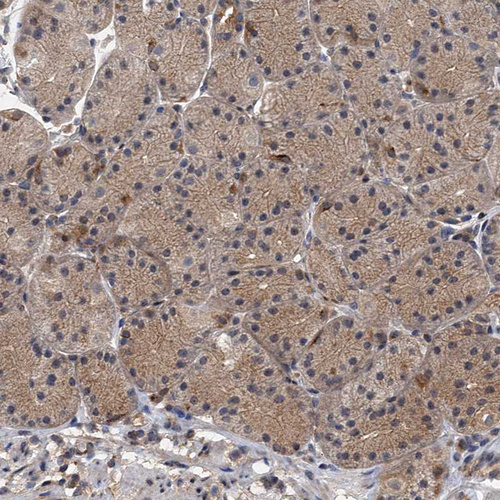

Immunohistochemistry analysis in human cerebral cortex and liver tissues using HPA040385 antibody. Corresponding NBEA RNA-seq data are presented for the same tissues.